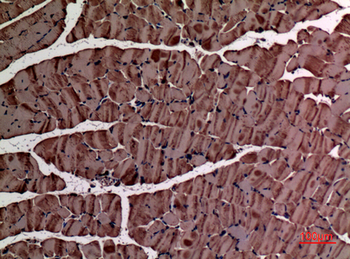

α-SMA Polyclonal Antibody

Catalog Number: orb1411650

| Catalog Number | orb1411650 |

|---|---|

| Category | Antibodies |

| Description | Rabbit polyclonal antibody to α-SMA. |

| Clonality | Polyclonal |

| Species/Host | Rabbit |

| Conjugation | Unconjugated |

| Reactivity | Human, Mouse, Rat |

| UniProt ID | P68133 |

| Tested applications | IHC-P, WB |

| Dilution range | WB: Western Blot: 1/500 - 1/2000. IHC-p: 1:100-300 ELISA: 1/20000. Not yet tested in other applications. |

| Storage | Maintain refrigerated at 2-8°C for up to 2 weeks. For long term storage store at -20°C in small aliquots to prevent freeze-thaw cycles |

| Alternative names | ACTA1; ACTA; Actin, alpha skeletal muscle; Alpha-a Read more... |

| Note | For research use only |